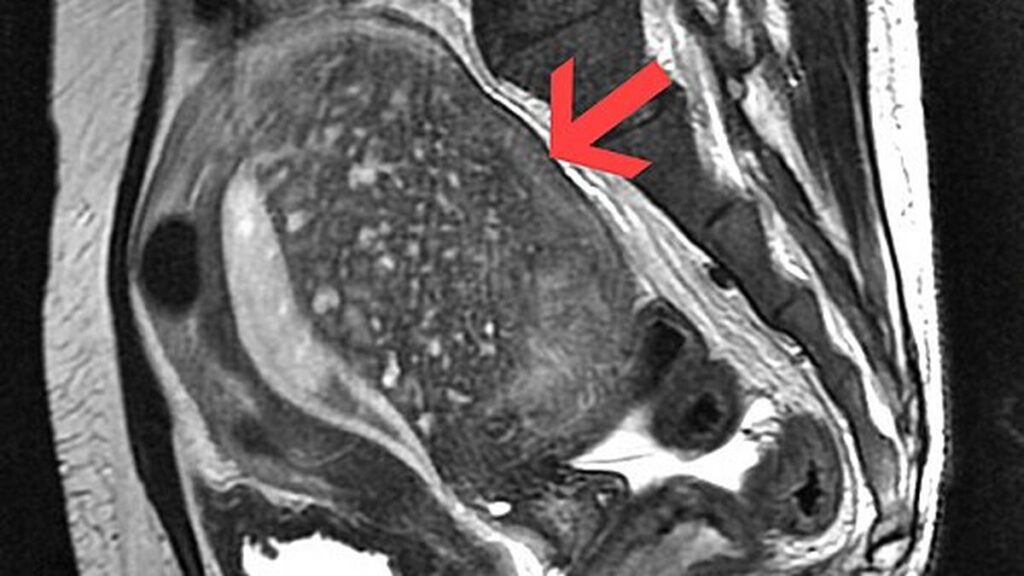

विशेषज्ञों का कहना है कि एडेनोमायोसिस का सही और त्वरित निदान इसके प्रबंधन के लिए आवश्यक है। हालांकि पारंपरिक चिकित्सीय परीक्षणों के जरिए इसका पता लगाने में कठिनाई होती है, परन्तु हाल के सुधारों में अल्ट्रासाउंड और एमआरआई जैसी तकनीकों के इस्तेमाल से निदान की प्रक्रिया बेहतर हुई है।